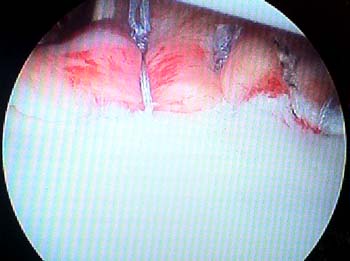

Figura 5: A: Esquema de cirugía de remplissage, fijación capsula posterior e infraespinoso en defecto de Hill Sach. B: Visión artroscópica desde el portal anterosuperior, se observa cobertura del defecto posterior a remplissage.

Figura 6: Visión artroscópica desde el portal anterosuperior, se observa, defecto de Hill-Sach y la colocación de primera sutura de anclaje en el defecto.